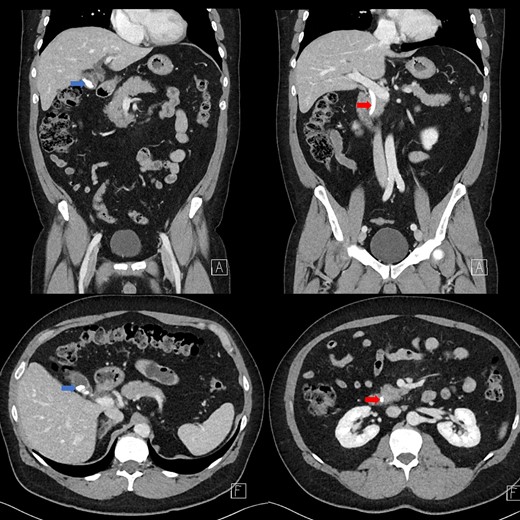

Portal venous contrast enhanced computed tomography (CT) of the abdomen revealed a layered dependent hyperattenuating material within the biliary tree (Fig. 1). The common bile duct (CBD) was dilated measuring 7.5 mm in diameter and filled along its course with radiodense material. Mild distention of the cystic duct and intrahepatic biliary tree were also noted with a 4 mm calculus in the CBD at the level of the duodenal ampulla (Fig. 2). There was no radiological evidence of cholecystitis.

CT demonstrating an obstructing calculus (right image) present within the CBD distinct from the limy bile (left image) (WW 2249, WL 450).